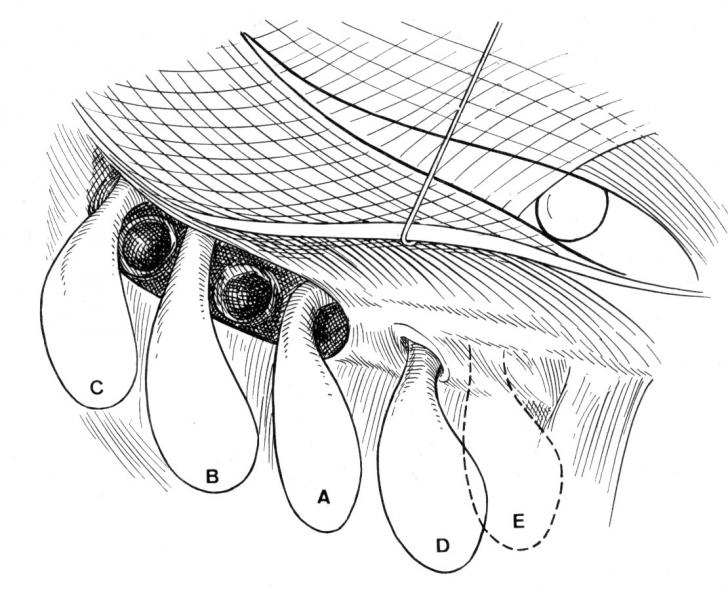

CURA CHIRURGICALA A HERNIILOR FEMURALE

CURA CHIRURGICALA A HERNIILOR FEMURALE I. DEFINITIE Cura chirurgicala a herniei femurale reprezinta interventia chirurgicala prin care se realizeaza suprimarea unei hernii crurale. Hernia femurala, hernie dobandita, prin slabiciune, mai fCiteste tot ... 2248 cuvinte

Dimensiune medie

+ cu poze |